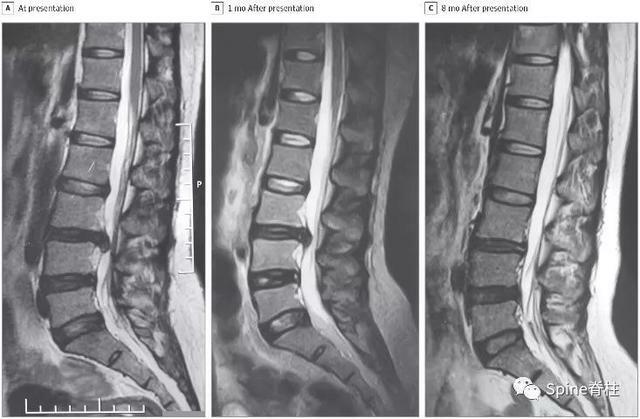

患者29歲,女,因「右小腿疼痛並感覺異常」就診,大小便正常。起始腰椎磁共振提示腰4-5椎間盤突出並椎管狹窄,神經根壓迫嚴重(左圖)。她選擇保守治療,5個月後,複查腰椎磁共振驚奇的發現突出的椎間盤被吸收了,且臨床症狀完全緩解。